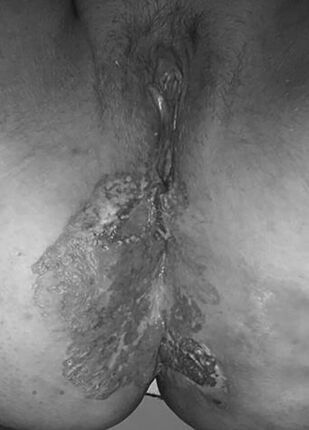

Vulva diseases. Risk factors, diagnosis, prevention, treatment

The study guide provides information about epidemiology, risk factors, diagnosis, prevention, and treatment of benign and malignant vulva diseases, clinical laboratory and instrumental methods for early diagnosis and treatment of vulva diseases. Th e timely detection of benign and precancerous vulva diseases and the initial stages can reduce mortality from vulvar cancer, economic losses associated with late initiation of treatment.

Th e study guide is intended for general practitioners, obstetricians and gynecologists, surgeons, oncologists, and doctors of other specialties.